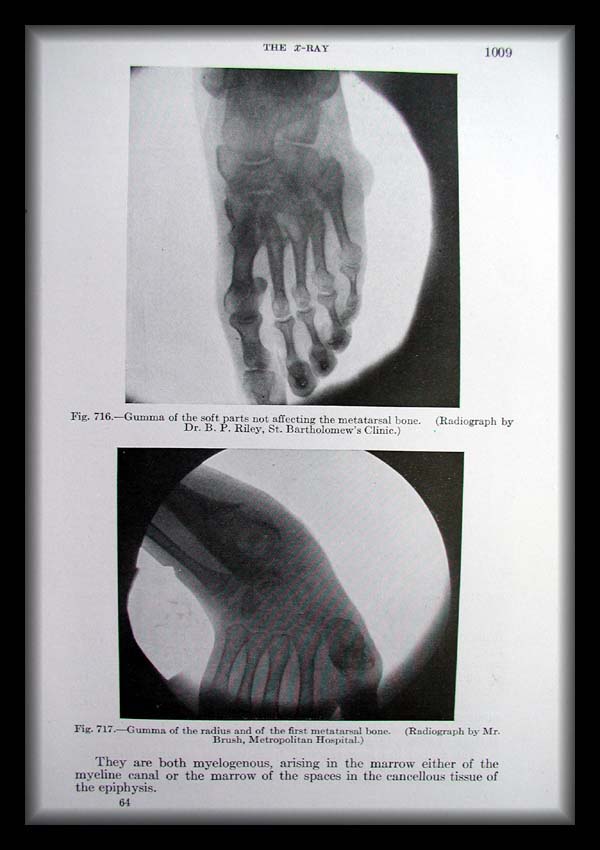

Page1009